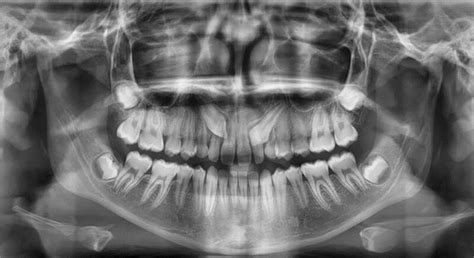

- Evaluación Diagnóstica: Radiografías y exámenes clínicos para determinar la posición exacta del canino incluido y su relación con las estructuras adyacentes.